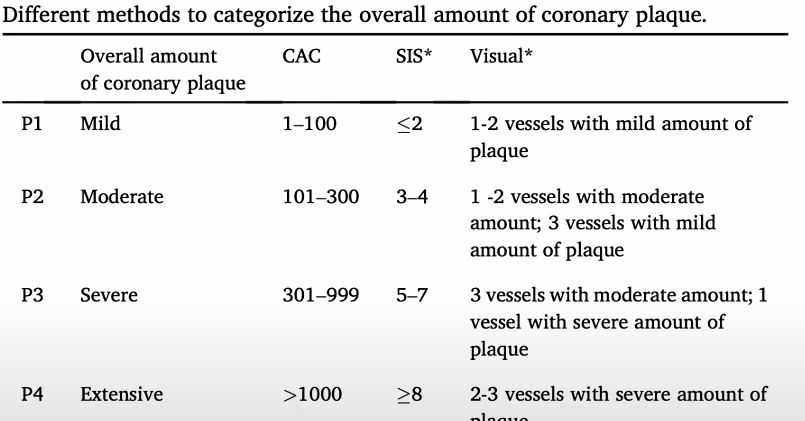

Plaque Burden P(0-4) / HRP

- Le plus simple = par le CAC score Agatson,

- Inclure aussi les plaques à haut risques (HRP) chez les non calcifiées

- HRP = si deux signes de plaque à risque

- P3 et P4 = indication a ttt medicamenteux agressif (statines, anti plaquettaires)

- SIS = Segment involvment score (nombre de segments atteints)